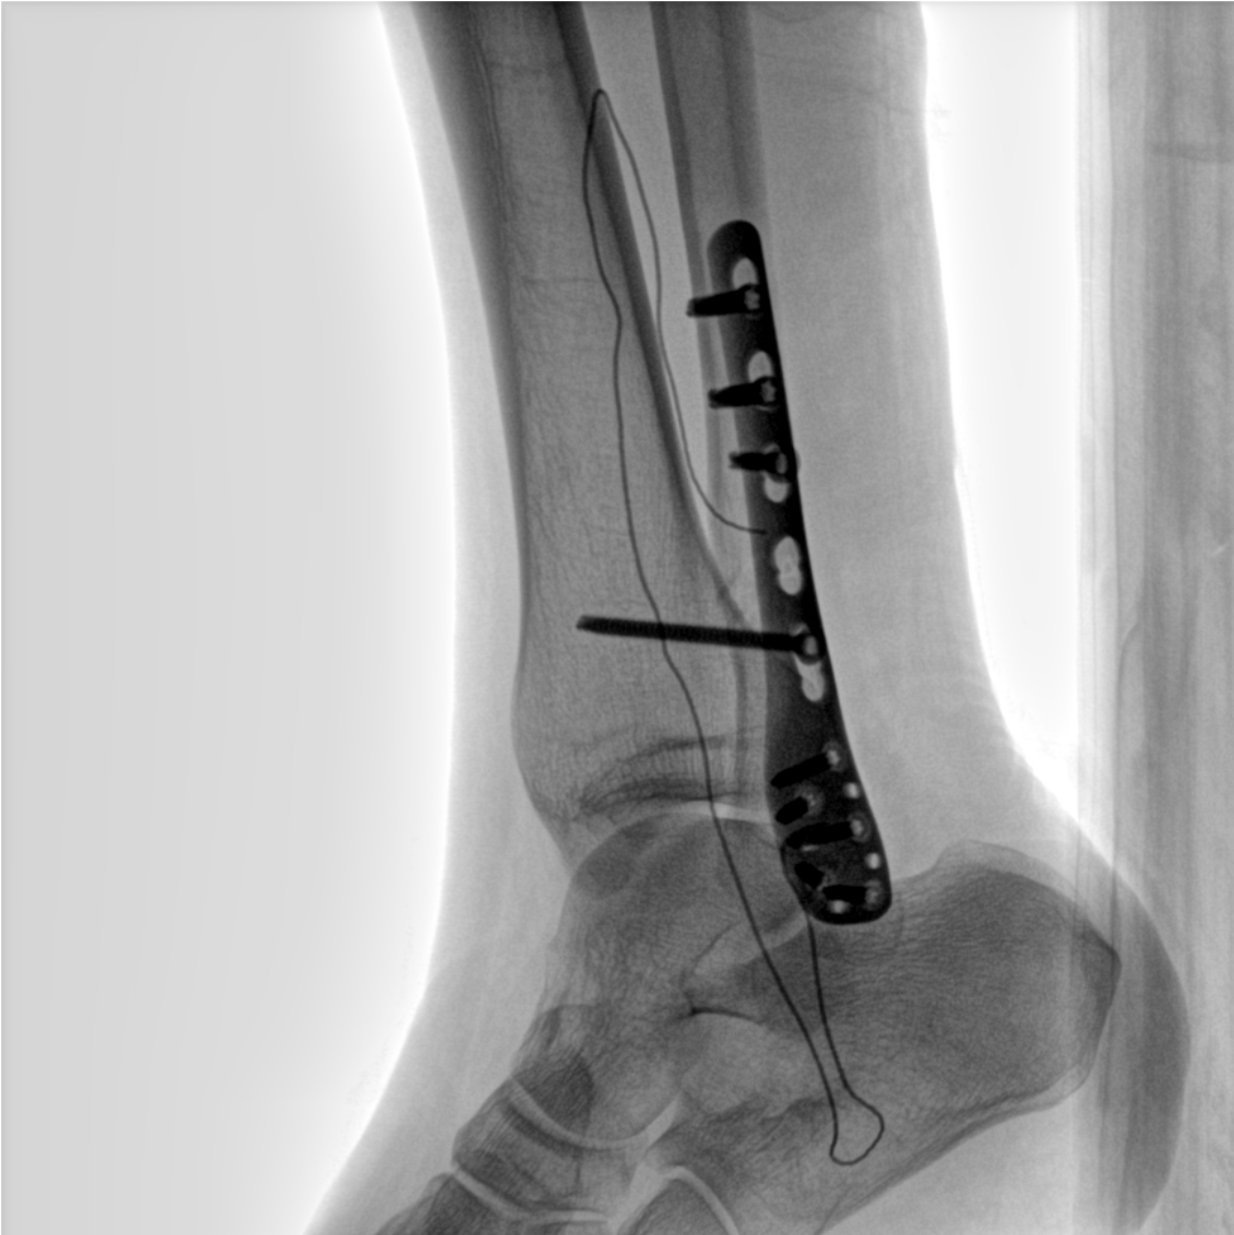

術(shù)中三維成像和橫斷面圖像提供多角度的手術(shù)診斷信息,輔助醫生進(jìn)行術(shù)中評估判斷,諸如骨折復位情況和內植入螺釘的尺寸和位置,輔助手術(shù)更好地完成。

在C臂掃描過(guò)程中,始終保持拍攝主體處于射線(xiàn)束的中心,避免了序列圖像采集過(guò)程中的橫縱方向運動(dòng),減少相對運動(dòng)造成的運動(dòng)偽影。